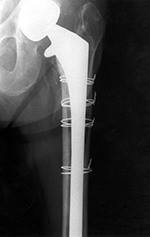

Cerclage wires |

A long stem bipolar hip prosthesis has cerclage wires in the diaphysis of the femur. From Benjamin, 1994 |